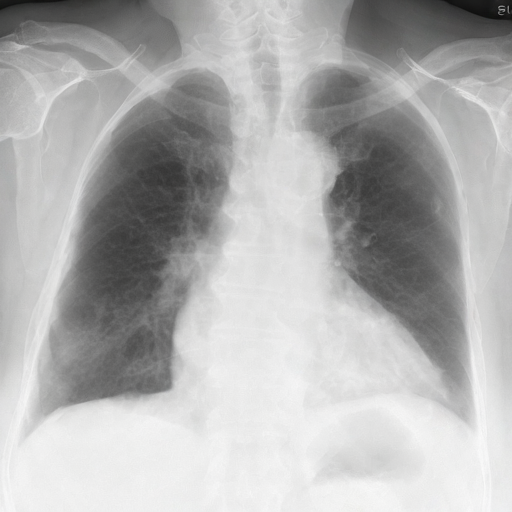

Let's load an example image of a patient with influenza.

RadEdit Edited Inputs

For this example, we will remove the visual appearance of influence from the lungs, while preventing changes from happening to the rest of the image. To do this, we create a mask of the lung regions and use this as the edit_mask which defines the region we wish the editing prompt to be applied to. Since we want the rest of the image to remain unchanged, we use the inverse as the keep_mask which defines the region where edits are discouraged from taking place.